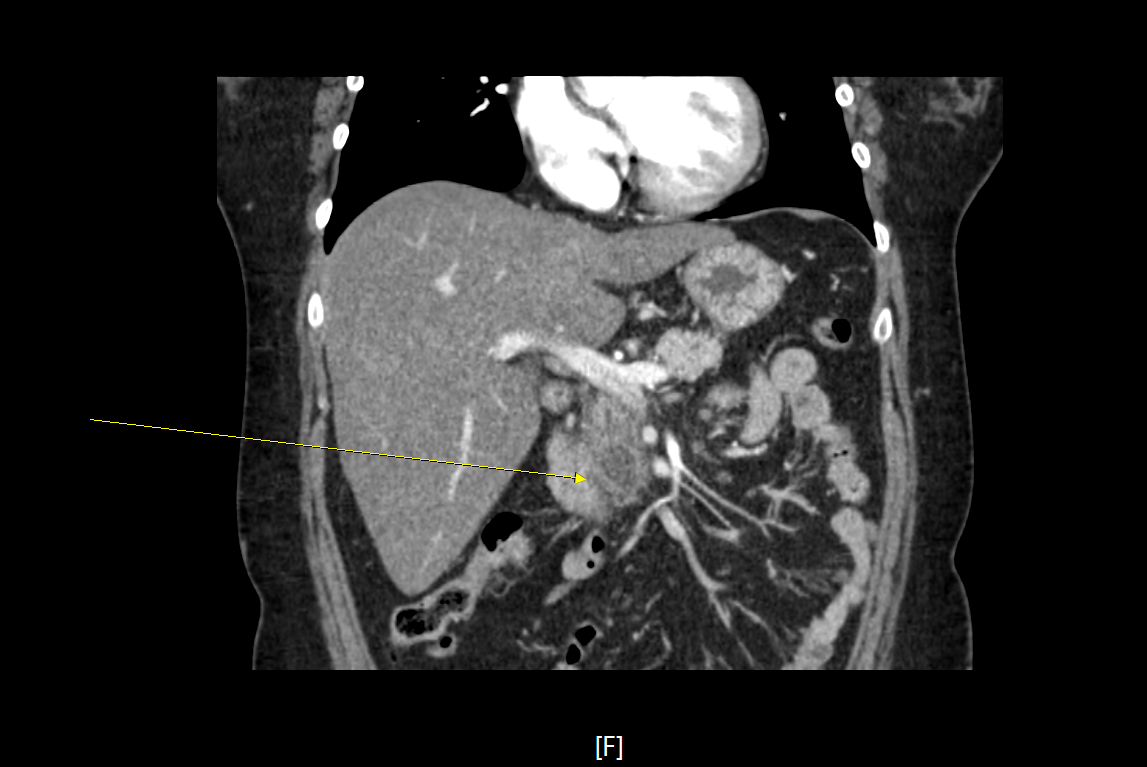

2-3. 영상검사에서 전형적인 소견

1) 복부 전산화단층촬영(CT), 자기공명영상(MRI), 복부 초음파(abdomen USG/SONO)

2) 복부 전산화단층촬영 : 급성 췌장염의 진단에 가장 중요한 영상검사로 혈청 amylase가 정상인 경우 췌장염의 진단에 필수적이다. 영상 소견을 통해 췌장의 괴사, 가성낭종(pseudocyst), 췌장성 복수와 같은 합병증도 함께 확인할 수 있어 유용하다.

3-2. 영상소견에 따른 분류

1) 간질성 부종성 췌장염 (interstitial edematous pancreatitis)

- 췌장괴사의 증거가 보이지 않은 췌장실질의 염증성 변화

- CT에서 조영제에 의한 췌장실질의 조영증가로 나타남.

- 국소 합병증으로 췌장 주변의 액체 저류 소견인 fluid collection과 낭종벽을 형성한 가성낭종(pseudocyst)을 형성키도 한다.

2) 괴사성 췌장염 (necrotizing pancreatitis)

- 염증으로 인한 췌장실질 및 췌장주위조직의 괴사

- 이미 괴사된 조직으로 조영제에 의해 조영증강 되지 않음.

- 국소 합병증으로 췌장 주변으로 궤사조직이 저류 되는 necrotic collection을 보이거나, 췌장괴사조직이 벽을 형성한 경우 walled-off necrosis소견을 보이기도 한다.

4-4. 복부 전산화단층촬영(Abdomen CT)

- 경증 췌장염에서는 불필요.

- 전형적인 증상 발생 4일 이내 시행하는 경우 타 질환으로 진단되는 경우는 거의 없으며, 괴사 여부, 합병증 여부 판정에 도움을 주지 않는다.

- CT를 시행해야 하는 경우

1) 췌장염의 진단이 불확실할 때

2) 중증(severe) 췌장염인 경우

3) 보존적 치료에 반응이 없거나 악화되어 중재 치료(Intervention)가 필요한 경우

- 가능하면 췌담도 질환에 대한 변별력을 높이기 위해 arterial, portal, venous phase를 촬영하는 3-phase CT의 촬영을 추천함.